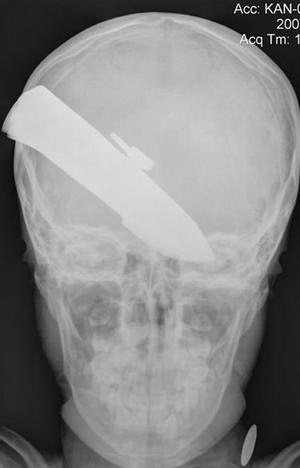

Афганский мальчик прожил год с ножом в голове.

Врачи, увидев рентгеновский снимок, пришли в ужас.

Как сообщает The Sidney Morning Herald, военные хирурги из полевого госпиталя в провинции Гельманд сделали рентгеновский снимок головы мальчугана и выяснили, что в черепе мальчугана застряло 7,5 см закаленной стали. Врачи были в ужасе.

- Лезвие проткнуло черепную коробку в затылочной части. Оно аккуратно прошло между двумя полушариями мозга, не повредив ни одно из них. Поэтому любая попытка вытащить нож из головы ребенка могла просто погубить его, - рассказали военные врачи.

Хирурги провели уникальную операцию и удалили лезвие. По словам отца пострадавшего, все произошло 14 июля 2007 года.

Написано чтонож попал между полушариями. но снимки отличаются, еси на первом можно предположить что он был там, то на втором нож вапще наискось воткнут...

на фото ножи разные! посмотрите на силуэт!